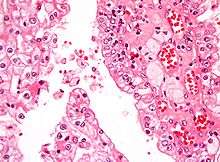

Micrograph showing the most common type of kidney cancer (clear cell renal cell carcinoma). H&E stain. | |

The two most common types of kidney cancer are renal cell carcinoma (RCC) and transitional cell carcinoma (TCC, also known as urothelial cell carcinoma) of the renal pelvis. These names reflect the type of cell from which the cancer developed.